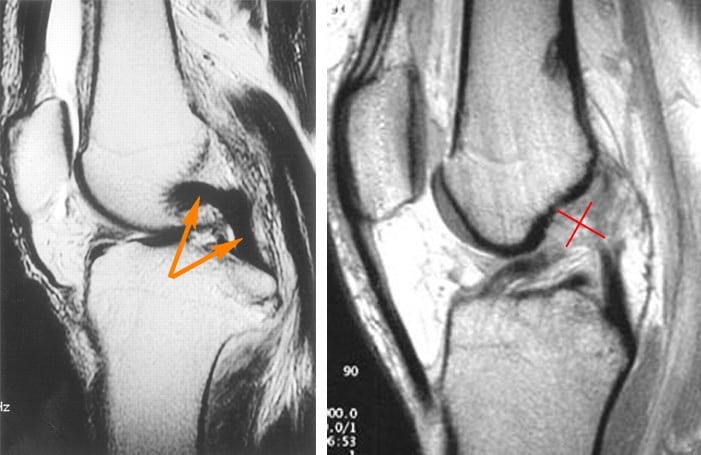

Для подтверждения первичного диагноза и оценки степени полученной больным травмы проводятся инструментальные исследования:

- рентгенография в передней, задней и боковой проекциях для исключения сопутствующих костных повреждений, например, отрывных переломов или образования трещин;

- КТ, МРТ для оценки состояния соединительнотканных структур колена, расположенных поблизости нервов, кровеносных сосудов, определения локализации разрыва.

Артроскопическое исследование сустава при острой травме затруднено. Полученные данные могут меняться от отсутствия деструкции тканей до полного повреждения задней крестообразной связки. При смещении разорванных волокон в медиальный отдел колена показана дифференциальная диагностика для исключения разрывов заднего рога медиального мениска.